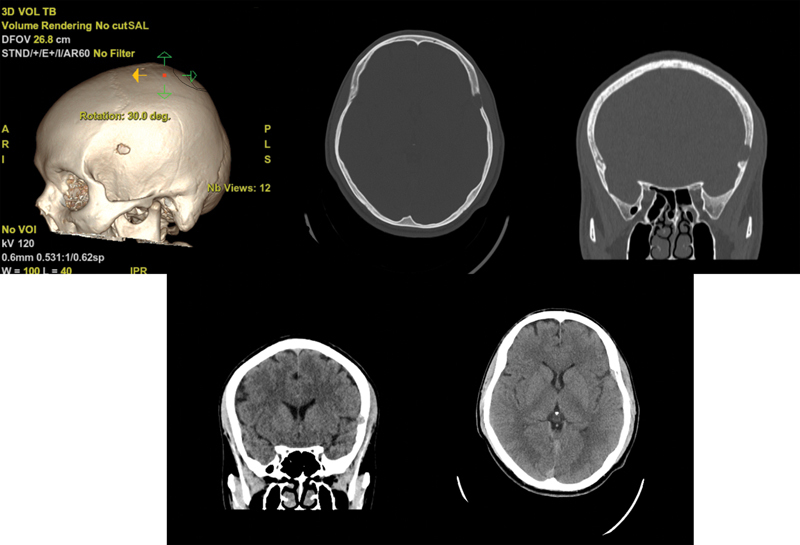

Introduction  Langerhans cell histiocytosis (LCH) is a rare proliferative systemic disease characterized by the growth of abnormal dendritic cells and wide-ranging organ involvement. This condition can affect individuals of all ages, but most commonly children, with a peak incidence in toddlers. Symptoms may vary depending on the affected organ or system. Case Report  A 43-year-old man presented with a left temporal stabbing headache unresponsive to management with therapy and nonsteroidal anti-inflammatory drugs. Initial evaluation revealed a contrast-enhanced left temporal extra-axial lesion with bone and muscle compromise. Differential diagnoses, including multiple myeloma, were explored. Initial laboratory tests and imaging studies showed no other abnormalities, except for splenomegaly and a residual granuloma in the left lung. En bloc resection of the lesion was recommended. The patient underwent surgical intervention, which included resection of the dural lesion and all borders of an infiltrating tumor within the temporalis muscle and the affected portion of the left temporal bone. Posterior pathological examination revealed LCH. Postoperative course was uneventful. Follow-up appointments were scheduled after pathology results confirmed the diagnosis. Patient has continued follow-up for the following 3 months after the surgical procedure. Further evaluations are pending. Discussion  This case report corresponds to a patient with LCH. These patients are individualized and stratified based on local or systemic involvement to determine the most appropriate type of management. This is a rare case as LCH is rare in older patients and the initial presented lesion initially mimicked a meningioma; however, its atypical behavior and associated lytic compromise led to consideration of possible differential diagnoses. Conclusion  LCH can present with lytic bone lesions, mimicking other conditions, including infiltrative neoplastic lesions. Early diagnosis and appropriate surgical management are essential for optimal patient outcomes. Long-term follow-up is crucial to monitor disease progression and response to treatment.

Abstract Image